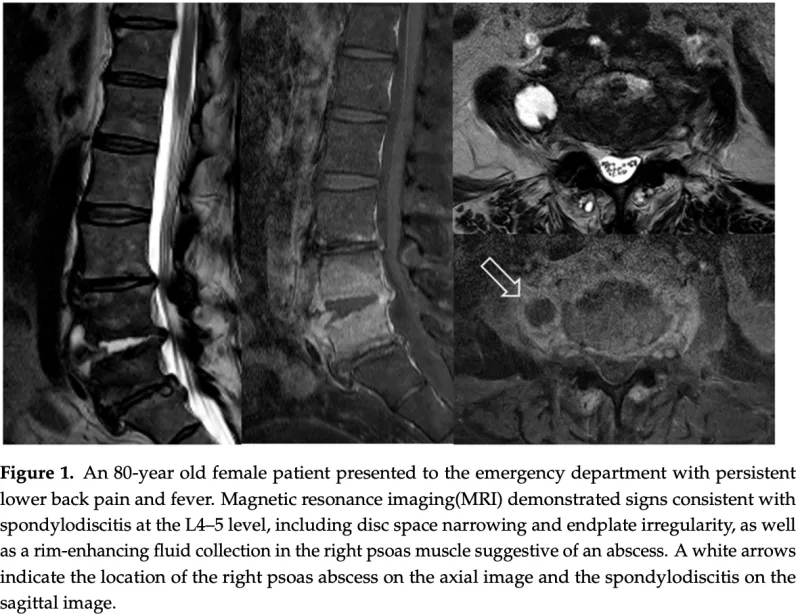

先週入院した高熱と腰痛の中高年患者さんの造影MRIを夕方に再度撮像したので確認.

第4/5腰椎椎間板に膿が貯まっていて, 白く写っている化膿性椎間板炎(左).

第4, 5腰椎が炎症によって全体に白く写っている化膿性脊椎炎(中央).

腰椎の右大腰筋(画像上は左)にT2強調像で白く(右上), ガドリニウム造影像で黒く抜けて写る(右下)のが大腰筋膿瘍.

その結果, 今回は明らかに所見があり, 第3/4腰椎椎間板炎, 第3, 4腰椎化膿性脊椎炎, 大腰筋膿瘍と診断.

発熱と腰痛の原因が判明して, スッキリしました.

解熱しており, 炎症の程度を示すCRP(C-反応性タンパク:基準値0.3 mg/dL以下)は, 先週24 mg/dLから今日は3.9 mg/dLまで低下しており, 抗菌薬が有効と判断して, 引き続き抗菌薬治療を行うことを説明.